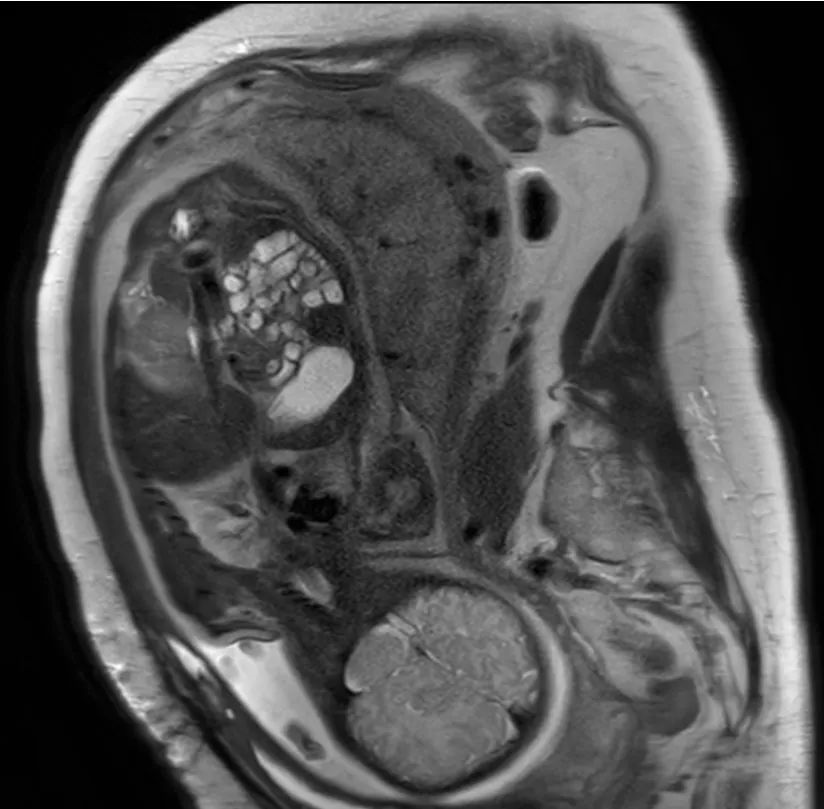

一群潜心于医学影像的生仪青年,正专注快速高分辨率的成像序列研发,在高场弥散磁共振的成像分辨率和成像速率上达到世界领先水平。如扩散磁共振能看到非常精细的大脑结构,为肿瘤等重大疾病治疗提供更好的技术手段。

科研小组从前端的成像技术和后端的图像处理技术两方面出发,开发出胎儿和婴幼儿的成像和后处理技术,拓展了胎儿大脑成像的新领域,成功克服胎儿运动伪影强的难题,实现了胎儿大脑的弥散成像和早期发育研究。